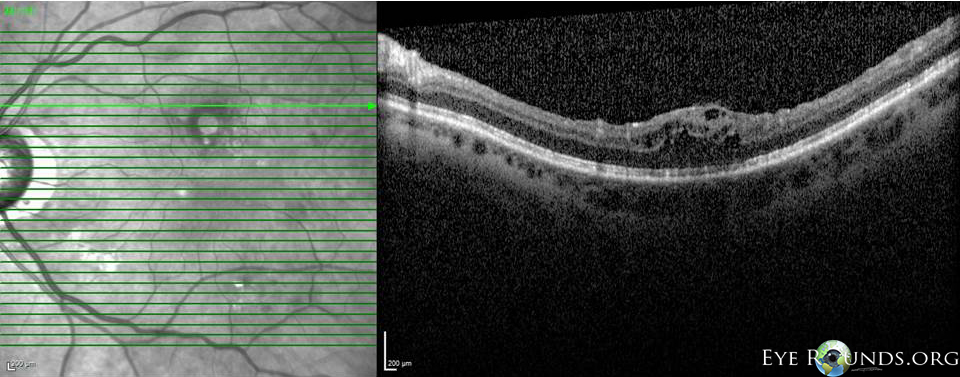

Fig 3-8: OCT OS: scant ERM remnants nasal to the fovea; thinning temporal in areas of prior membrane peeling.